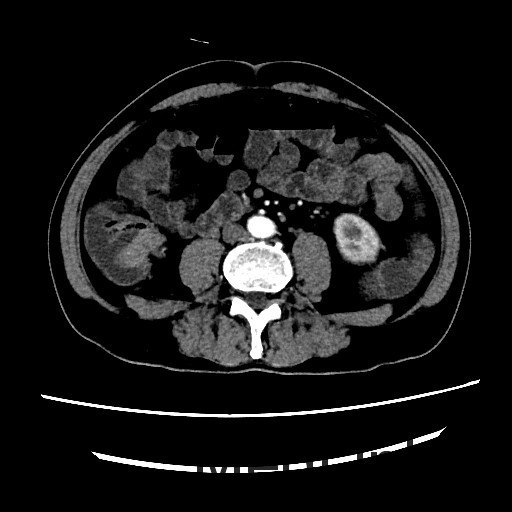

查体:腹平,腹软,肝区、双肾区无叩痛,腹部移动性浊音(-)。肠鸣音4次/分。双下肢无浮肿。 辅查:全腹螺旋CT平扫+增强:1、结肠肝区病变,考虑结肠癌,累及全层。2、直肠及乙状结肠病变,考虑炎症性病变。

讨论:本病例可以在CT冠状位看到结肠肝曲肠壁局限性增厚,属于浸润型结肠癌的表现,CT诊断结肠癌的时候,一般冠状位能够较好的显示结肠全貌,可以比较容易发现病灶,因此平常应先从冠状位发现胃肠道的病灶,再结合横断位诊断。作为影像医生除了报告癌肿,还需要注意一些临床关注的问题,比如癌肿与周围组织的关系,局部有无肿大淋巴结转移,其他脏器有无浸润或转移,在报告中提示这些情况,能够帮助临床选择合适的治疗方案。